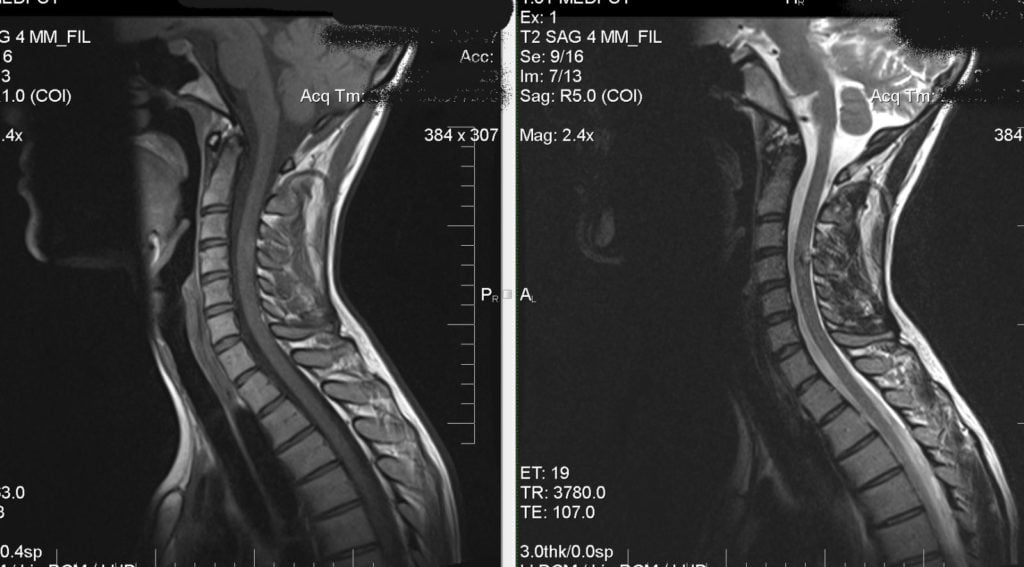

Наиболее информативна в выявлении шейного остеохондроза рентгенография. При жалобах пациента на скачки артериального давления обязательно проводятся МРТ головы и шеи, ультразвуковая допплерография кровеносных сосудов в шейном отделе.